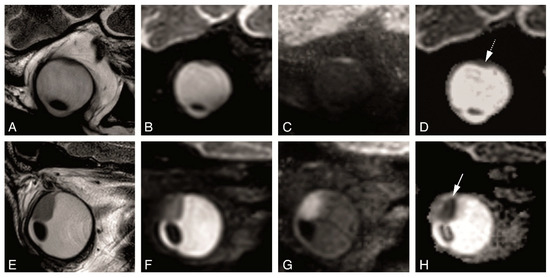

4.2. Anatomical MRI of Uveal Melanoma

4.3. Functional MRI of Uveal Melanoma